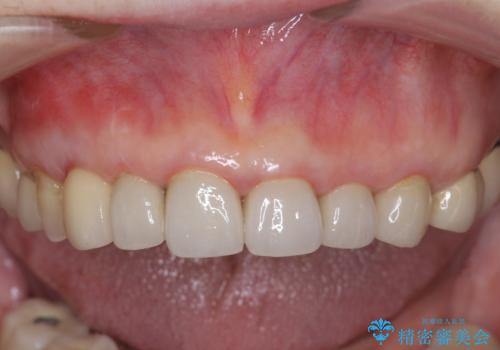

クラウン下に再発した深い虫歯 インプラントによる機能回復

前歯のインプラント治療について

前歯のインプラントを仕上げるには骨や歯ぐきの条件を整えることが肝要です。